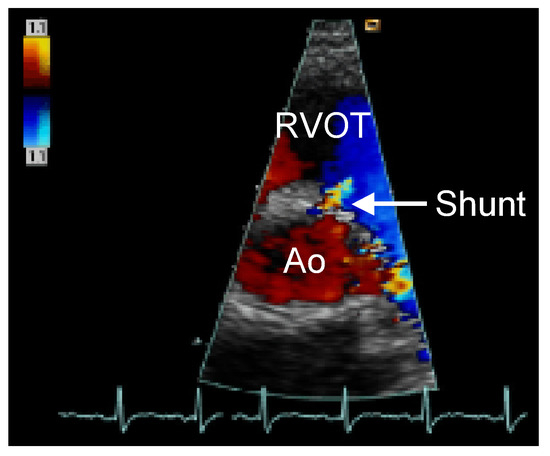

...und Immer Wieder Dieses Herzrasen!

by Michael K. Neuhaus, Hans o. Gloor, Marius Volkmer and Jürg Beer

Cardiovasc. Med. 2006, 9(6), 235; https://doi.org/10.4414/cvm.2006.01179 - 30 Jun 2006

Viewed by 51

Abstract

Ein 40jähriger Patient klagt seit 15 Jahren über rezidivierende tachykarde Palpitationen [...] Full article